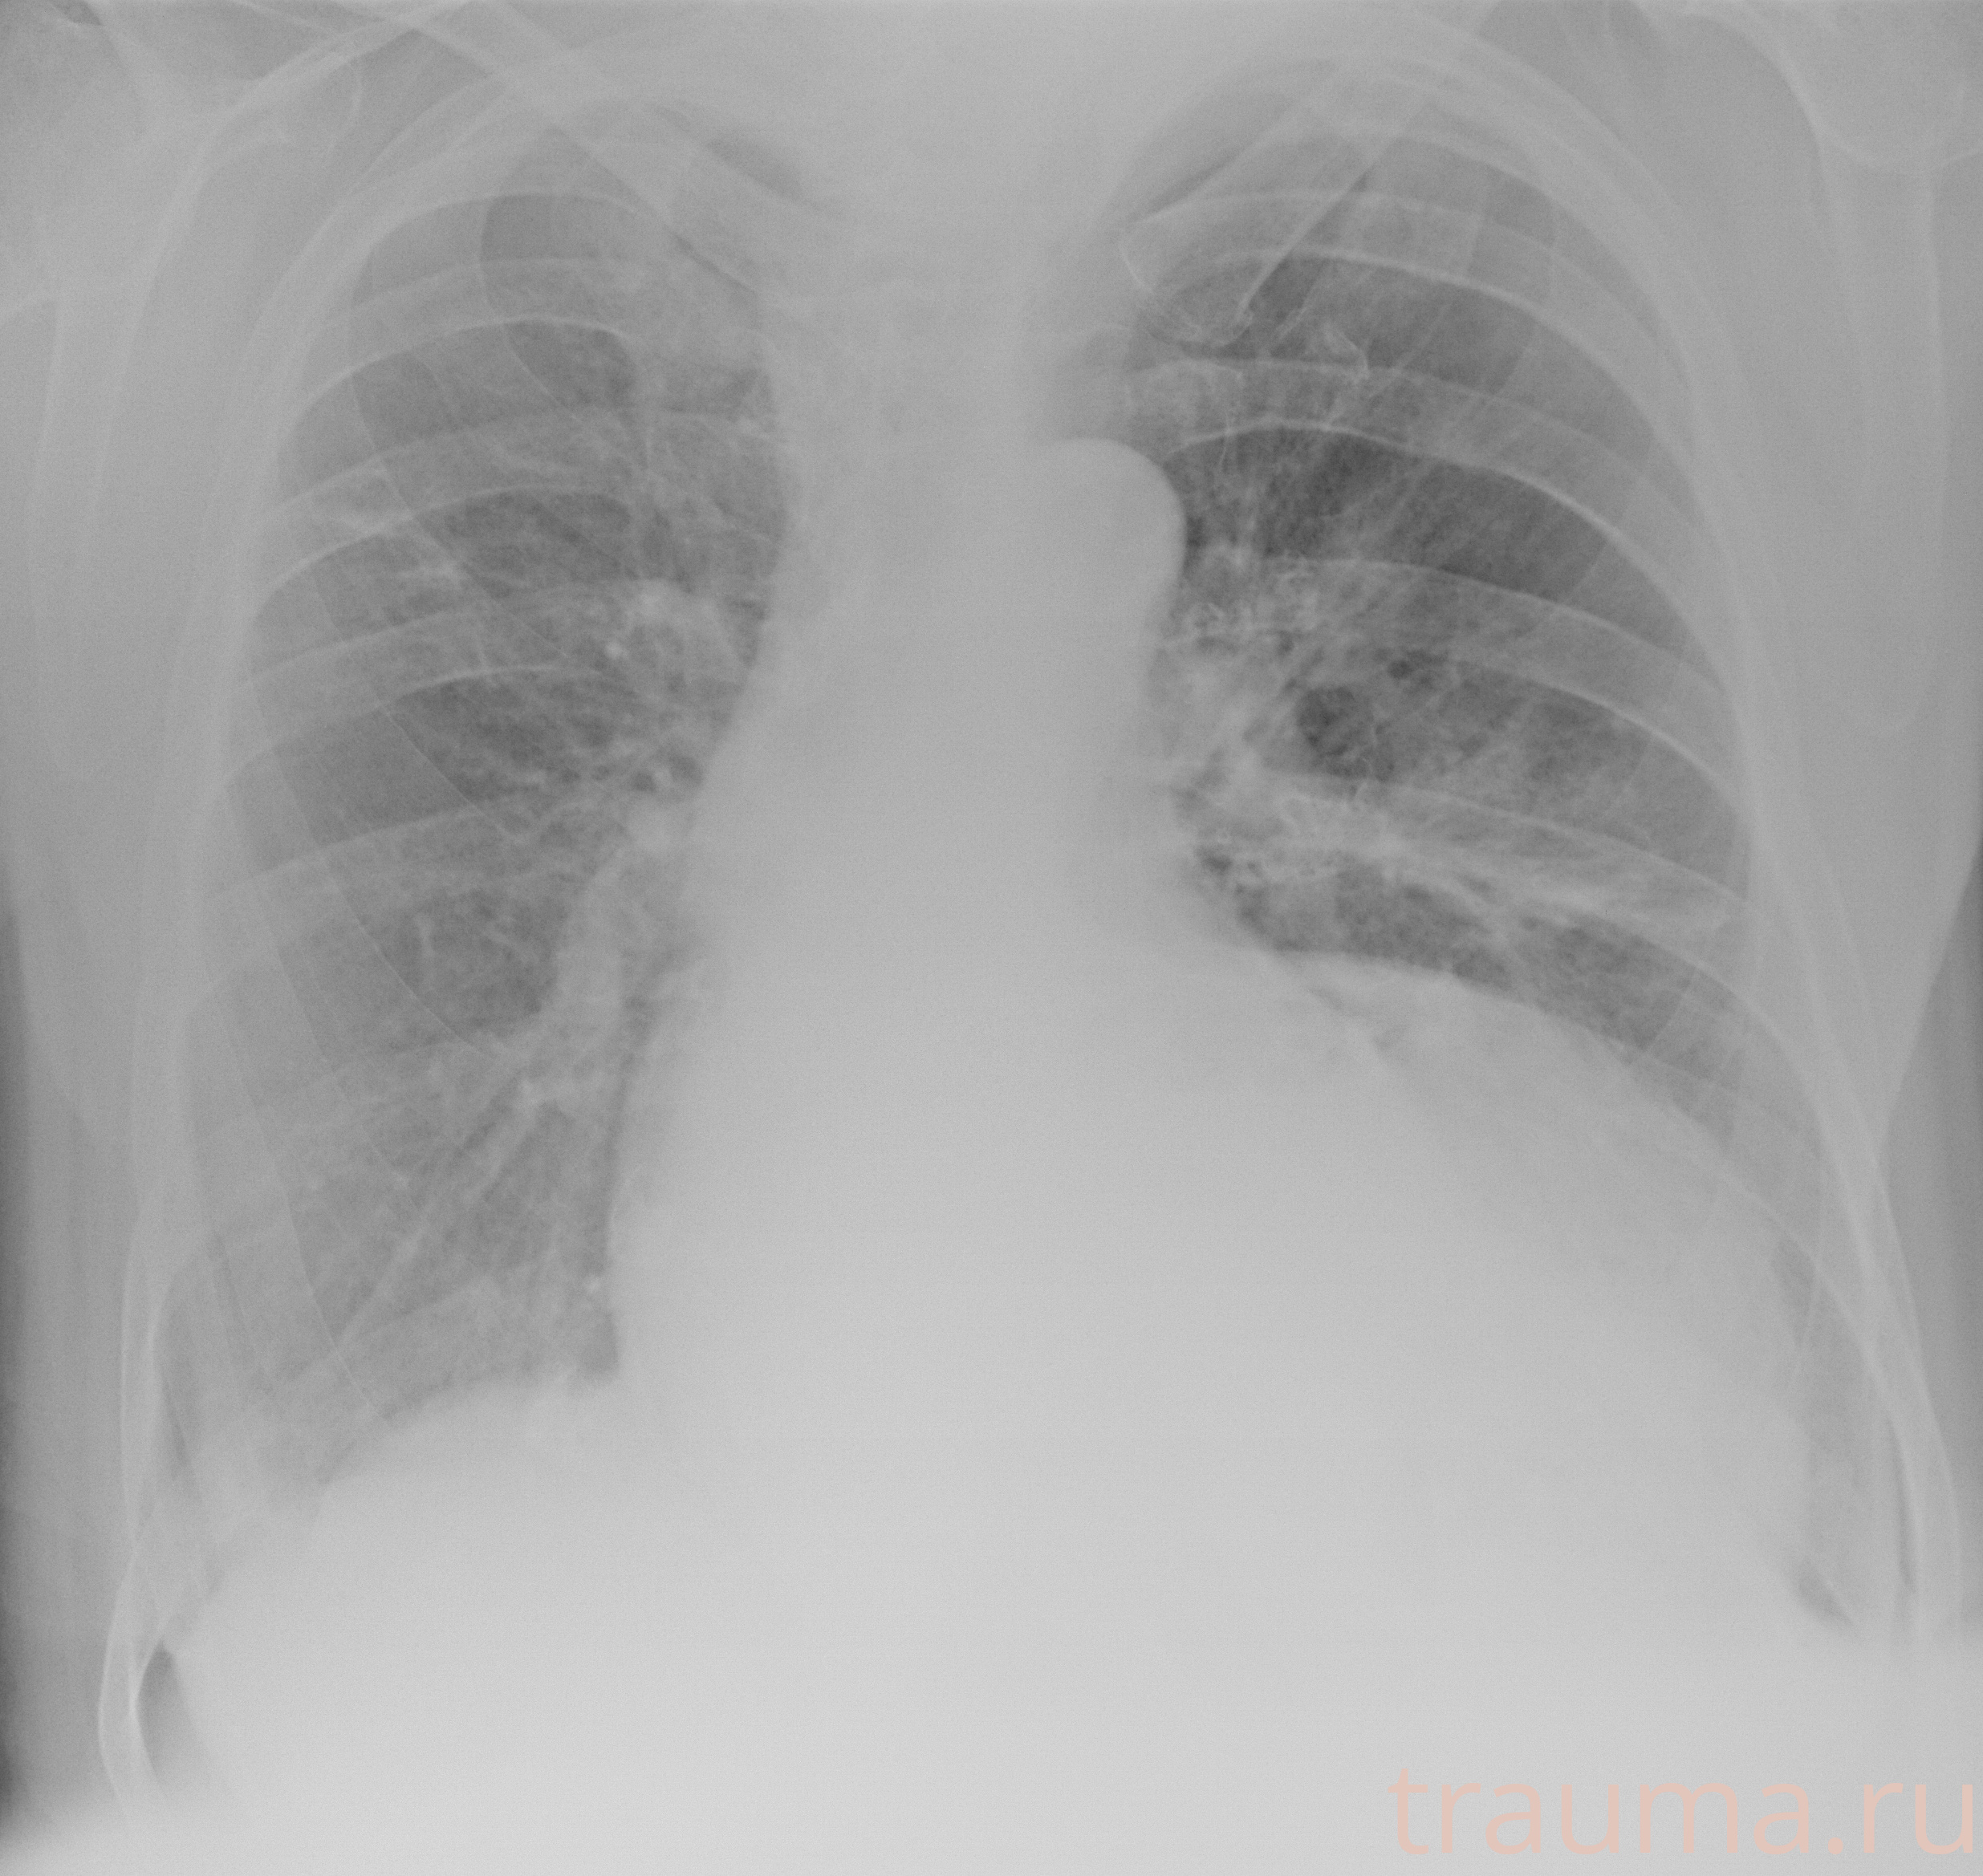

Рентгенограммы

Рентген на дому: по вашему адресу приезжает врач-рентгенолог, травматолог-ортопед с мобильным рентгеновским аппаратом, проводит диагностику травмы или заболевания, делает необходимые рентгенограммы, дает рекомендации по дальнейшему лечению. Получить качественные снимки в домашних условиях возможно благодаря уникальной методике, разработанной МосРентген Центром для института  Склифосовского